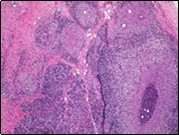

Figure 1.Granulomatous mastitis with the configuration of epitheloid cell granuloma and a lymphoid and plasma cell infiltrate9.

Core needle biopsy of idiopathic granulomatous mastitis enunciates multiple aggregates of non- caseating epitheloid cell granulomas within and encompassing breast lobules, constituted of epitheloid histiocytes, lymphocytes, neutrophils and multinucleated giant cells. Granulomatous inflammation is predominantly lobulo-centric. The inflammation is preponderantly composed of lymphocytes, plasma cells, epitheloid histiocytes, multinucleated giant cells and neutrophils. Neutrophils can configure micro-abscesses and encompass vacant micro-cystic cavities, morphological features which are in common with cystic neutrophilic granulomatous mastitis. Non specific lobulitis along with a lymphoid and plasma cell infiltrate accompanies the granulomatous inflammation. Necrosis is usually absent. Neutrophilic micro-abscesses can be accompanied by fistula formation 4, 5.

Multinucleated giant cells are detected in an estimated three fourths (78.5%) instances. Plasma cells are discernible in around half (53.9%) of the subjects and usually appear at the margins of cystic vacuoles with centric accumulation of neutrophils within the granulomas.